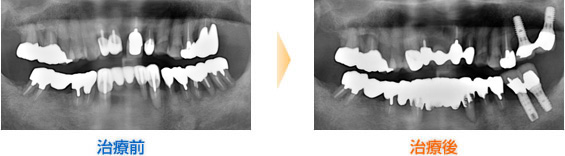

■40代男性

奥歯を虫歯によって失くされてから約10年間放置されていました。前歯だけで物を噛まれていましたが、最近になって前歯がグラグラしてきたため当院を受診されました。

嘔吐反射が強いため義歯を断念、インプラント治療(インプラント11本埋入)を受けられました。

治療後は何でも噛めるようになったため非常に満足されています。